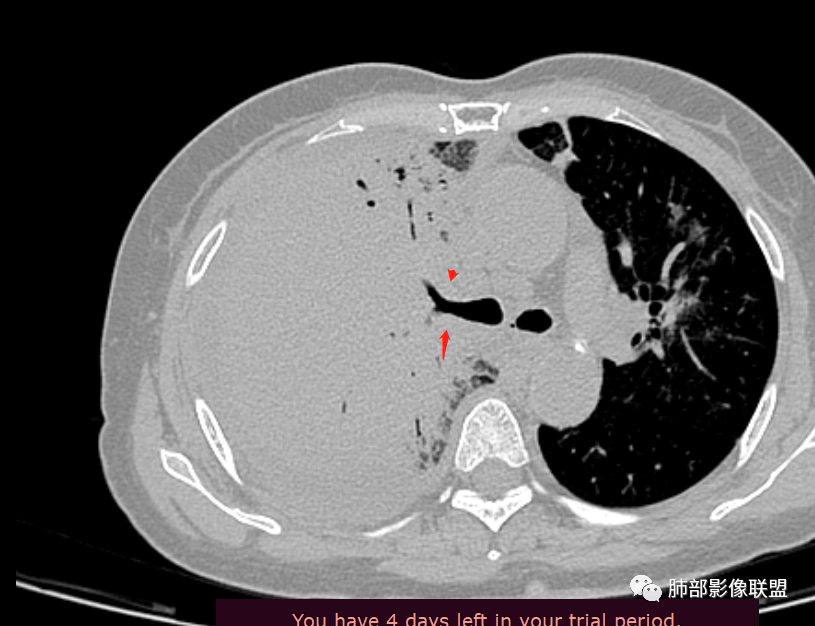

04 南边老师复盘

该病例,需要二元解释,这么高的白细胞提示感染,这个病例确实很怪。一是感染,还有淋巴瘤,一直在犹豫远端的空腔还是扩张支气管,如何形成的。这个看支气管及远端的泡。

这是扩张大支气管?还是囊腔?

空洞?

犹豫的点在于位置,与支气管关系。

南边:

一般空洞——应该在病灶的中央或实变区,这个在边缘。

囊腔?按理是近端支气管狭窄,导致气体潴留,不太符合。

如果能定到底是空洞还是空腔就好办。

因为大片实变支气管扩张原因:周围牵拉,支气管壁破坏。

这个在边缘,周围没有牵拉等因素,所以应该是壁的破坏。

壁破坏,这样的就需要观察整个壁的形态。

如果支气管看通透了,估计会朝二元论考虑。这个病例好,值得好好总结。